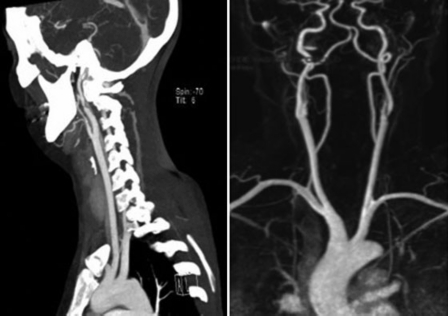

La Angio-TC y la Angio-RM son métodos complementarios, no invasivos, para estudiar la enfermedad carotídea. Además, aportan información anatómica de la porción intracraneal e intratorácica de los vasos del cuello. Ambas se basan en los criterios NASCET para la medición del grado de estenosis y son métodos de elección y complementarios en determinados pacientes (►Figs. 1 y 2).4 Esos criterios consisten en correlacionar el diámetro de la arteria carótida interna (ACI), en su sitio de máxima estenosis, con el de su segmento distal normal, donde ambas paredes se vuelven paralelas.

Angio-TC y Angio-RM de vasos de cuello (A y B).